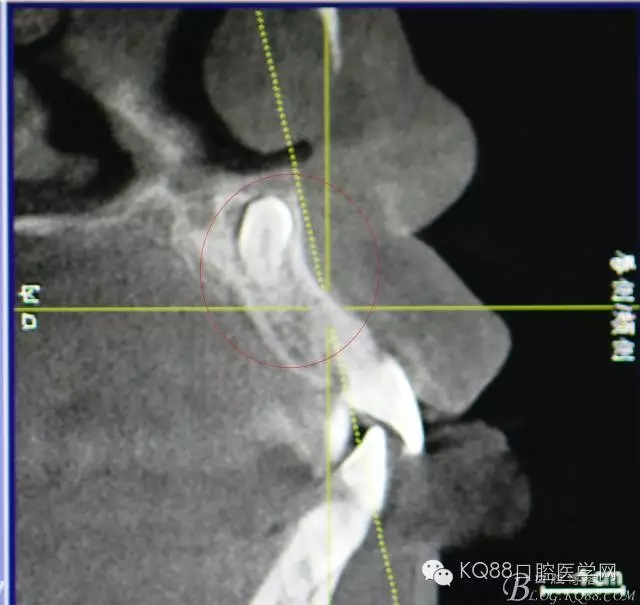

圖2.CBCT矢狀面影像檢查:多生牙牙冠上方與鼻底僅有黏膜相隔

圖3.CBCT三個(gè)方向剖面圖影像:多生牙牙根阻擋11內(nèi)收、牙冠接近鼻底

圖4.cbct的三維重建影像:多生牙牙尖幾乎和鼻底相通